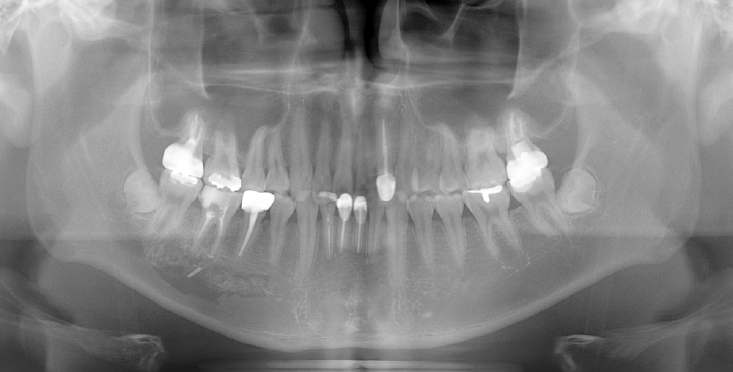

A 73-year-old male was referred after endodontic treatment of the mandibular right second molar (#47) with severe post-treatment pain. Evidence of Calcipex II extrusion into the IAN canal was evident on the panoramic radiograph and CBCT. (Fig. 8). Root canal treatment was done about 2 months ago. He underwent foreign body removal under general anesthesia (Fig. 9). Postoperatively, he reported minimal change in numbness symptoms. He was lost to follow-up but returned six months later complaining of recurrent neuropathic symptoms and itching. Carbamazepine was prescribed. No follow-up sensory testing was performed.